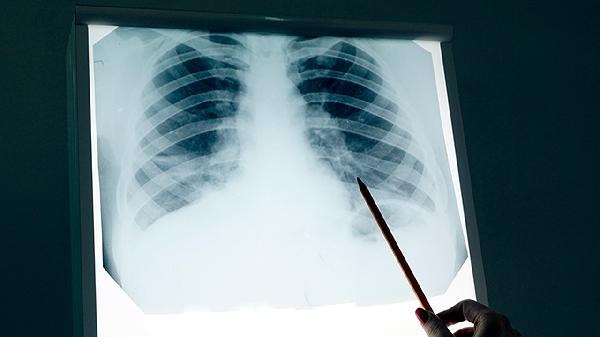

低分化肺癌中晚期怎么治疗

低分化肺癌中晚期可通过手术治疗、放射治疗、化学治疗、靶向治疗、免疫治疗等方式治疗。低分化肺癌通常由吸烟、环境污染、基因突变等因素引起,建议患者及时就医,积极配合医生治疗。